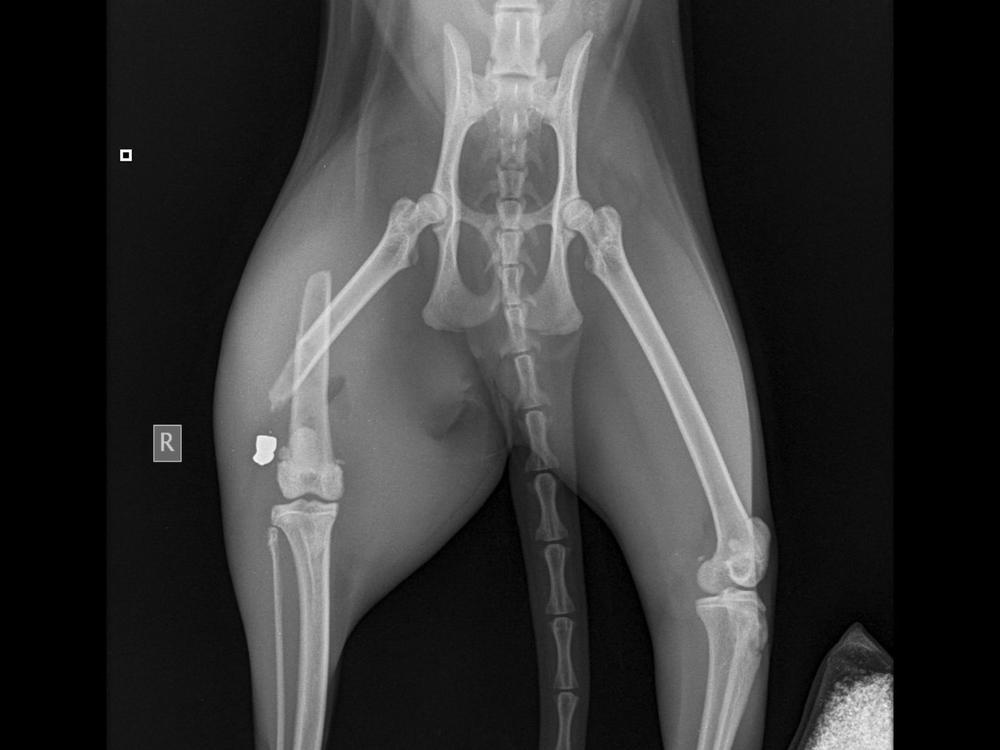

On Thursday March 19 Sonic was shot with a slug gun which has resulted in her leg being snapped in half. I had to rush my girl to the emergency vets which cost $900 and then she needed to have surgery which has cost $2660. There will also be ongoing costs for removing stitches, and having further xrays to check up on her leg, she will need to be sedated for this

The good news is that Sonic has been in for her final Xrays and the vets are happy with her recovery, she is 90% healed and is now able to roam around the house. Sonic is now an inside cat after what has happened.